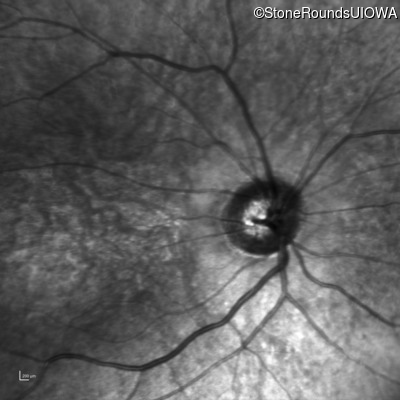

Infrared Fundus Photograph - Right - 10/200

Exemplar